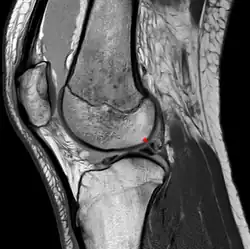

Posterior meniscofemoral ligament on MRI, sagittal -

Posterior meniscofemoral ligament (Wrisberg) behind the posterior horn of the lateral meniscus close to its insertion. Sometimes wrongly interpreted as a meniscal tear.